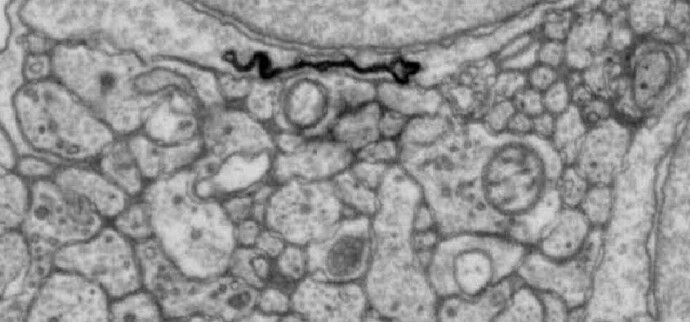

Ganglion cells from a human retina! Not our dataset but very cool - the cells look so similar!

https://x.com/retinavision/status/1909694859109347340?s=46&t=LRe5UDrWT3OpTPHjKfgaxA